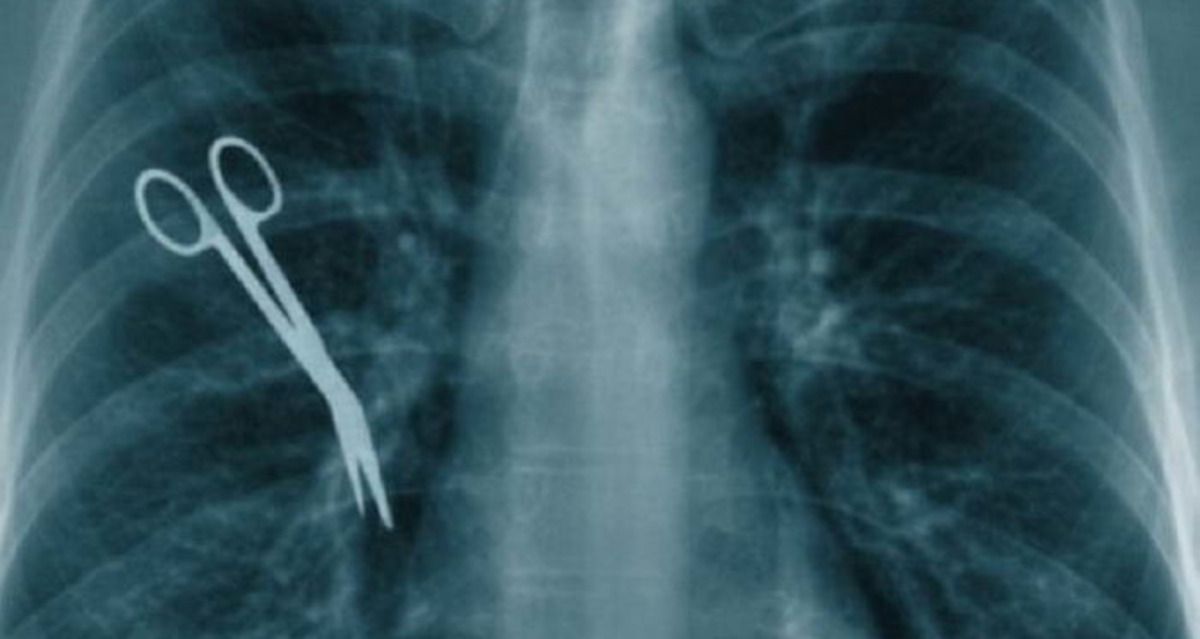

في واقعة إهمال طبية صادمة، اكتشفت كاملا باي، البالغة من العمر 44 عامًا، بعد عامين من إجرائها عملية جراحية لاستئصال سرطان المبيض، أن مقصًا جراحيًا نُسي داخل جسدها. هذا الاكتشاف الصادم كشف عن إهمال طبي فادح تعرضت له كاملا، حيث عاشت لفترة طويلة مع آلام شديدة في منطقة البطن رغم إجرائها الجراحة بنجاح. الأمر الذي دفعها لإجراء فحوصات طبية إضافية حتى تم اكتشاف الأداة الجراحية في جسمها عبر فحص التصوير المقطعي.

يعد ترك الأدوات الجراحية داخل جسم المريض أمرًا بالغ الخطورة، حيث يمكن أن يؤدي إلى مضاعفات صحية شديدة. من بين هذه المضاعفات النزيف الداخلي، العدوى، النخر، وفي الحالات المتقدمة قد تصل الأمور إلى الوفاة.

وفقًا للتقارير الطبية، يشكل وجود أداة حادة مثل المقص داخل الجسم تهديدًا حقيقيًا لحياة المريض، وهو ما عانت منه كاملا طوال فترة معاناتها من الألم المستمر جراء إهمال طبي غير مسبوق.